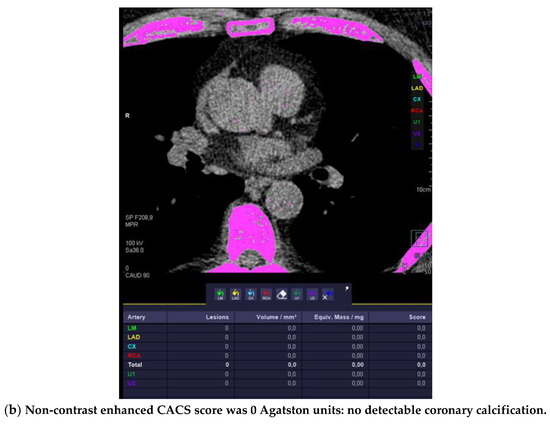

2.1.1. Coronary Artery Calcium Score (CACS)